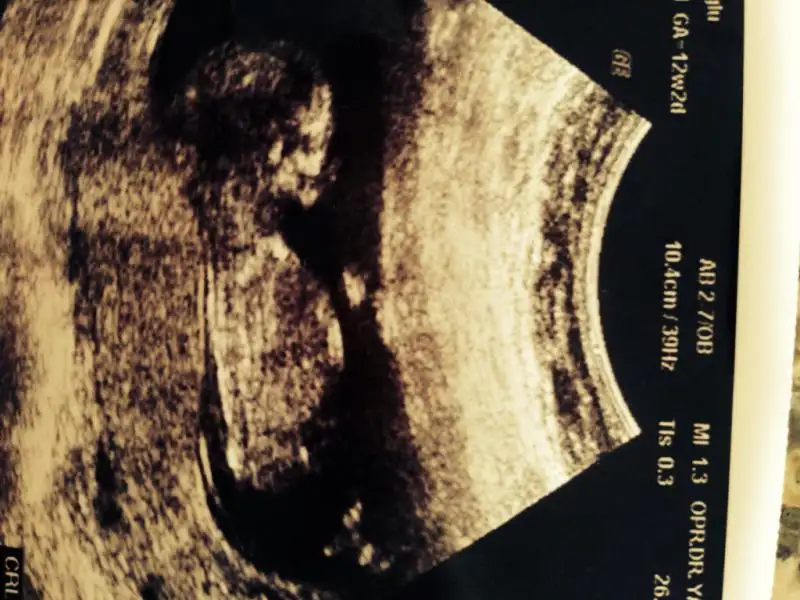

resim 1

Eki Görüntüle 473828 gordugunuz gibi ust taraftaki simgedende anlasildigi gibi eger cikinti paralel ise kiz

yok 30°lik bir aciyla yukari dogru bakiyorsa %99 oglunuz olacak demektir